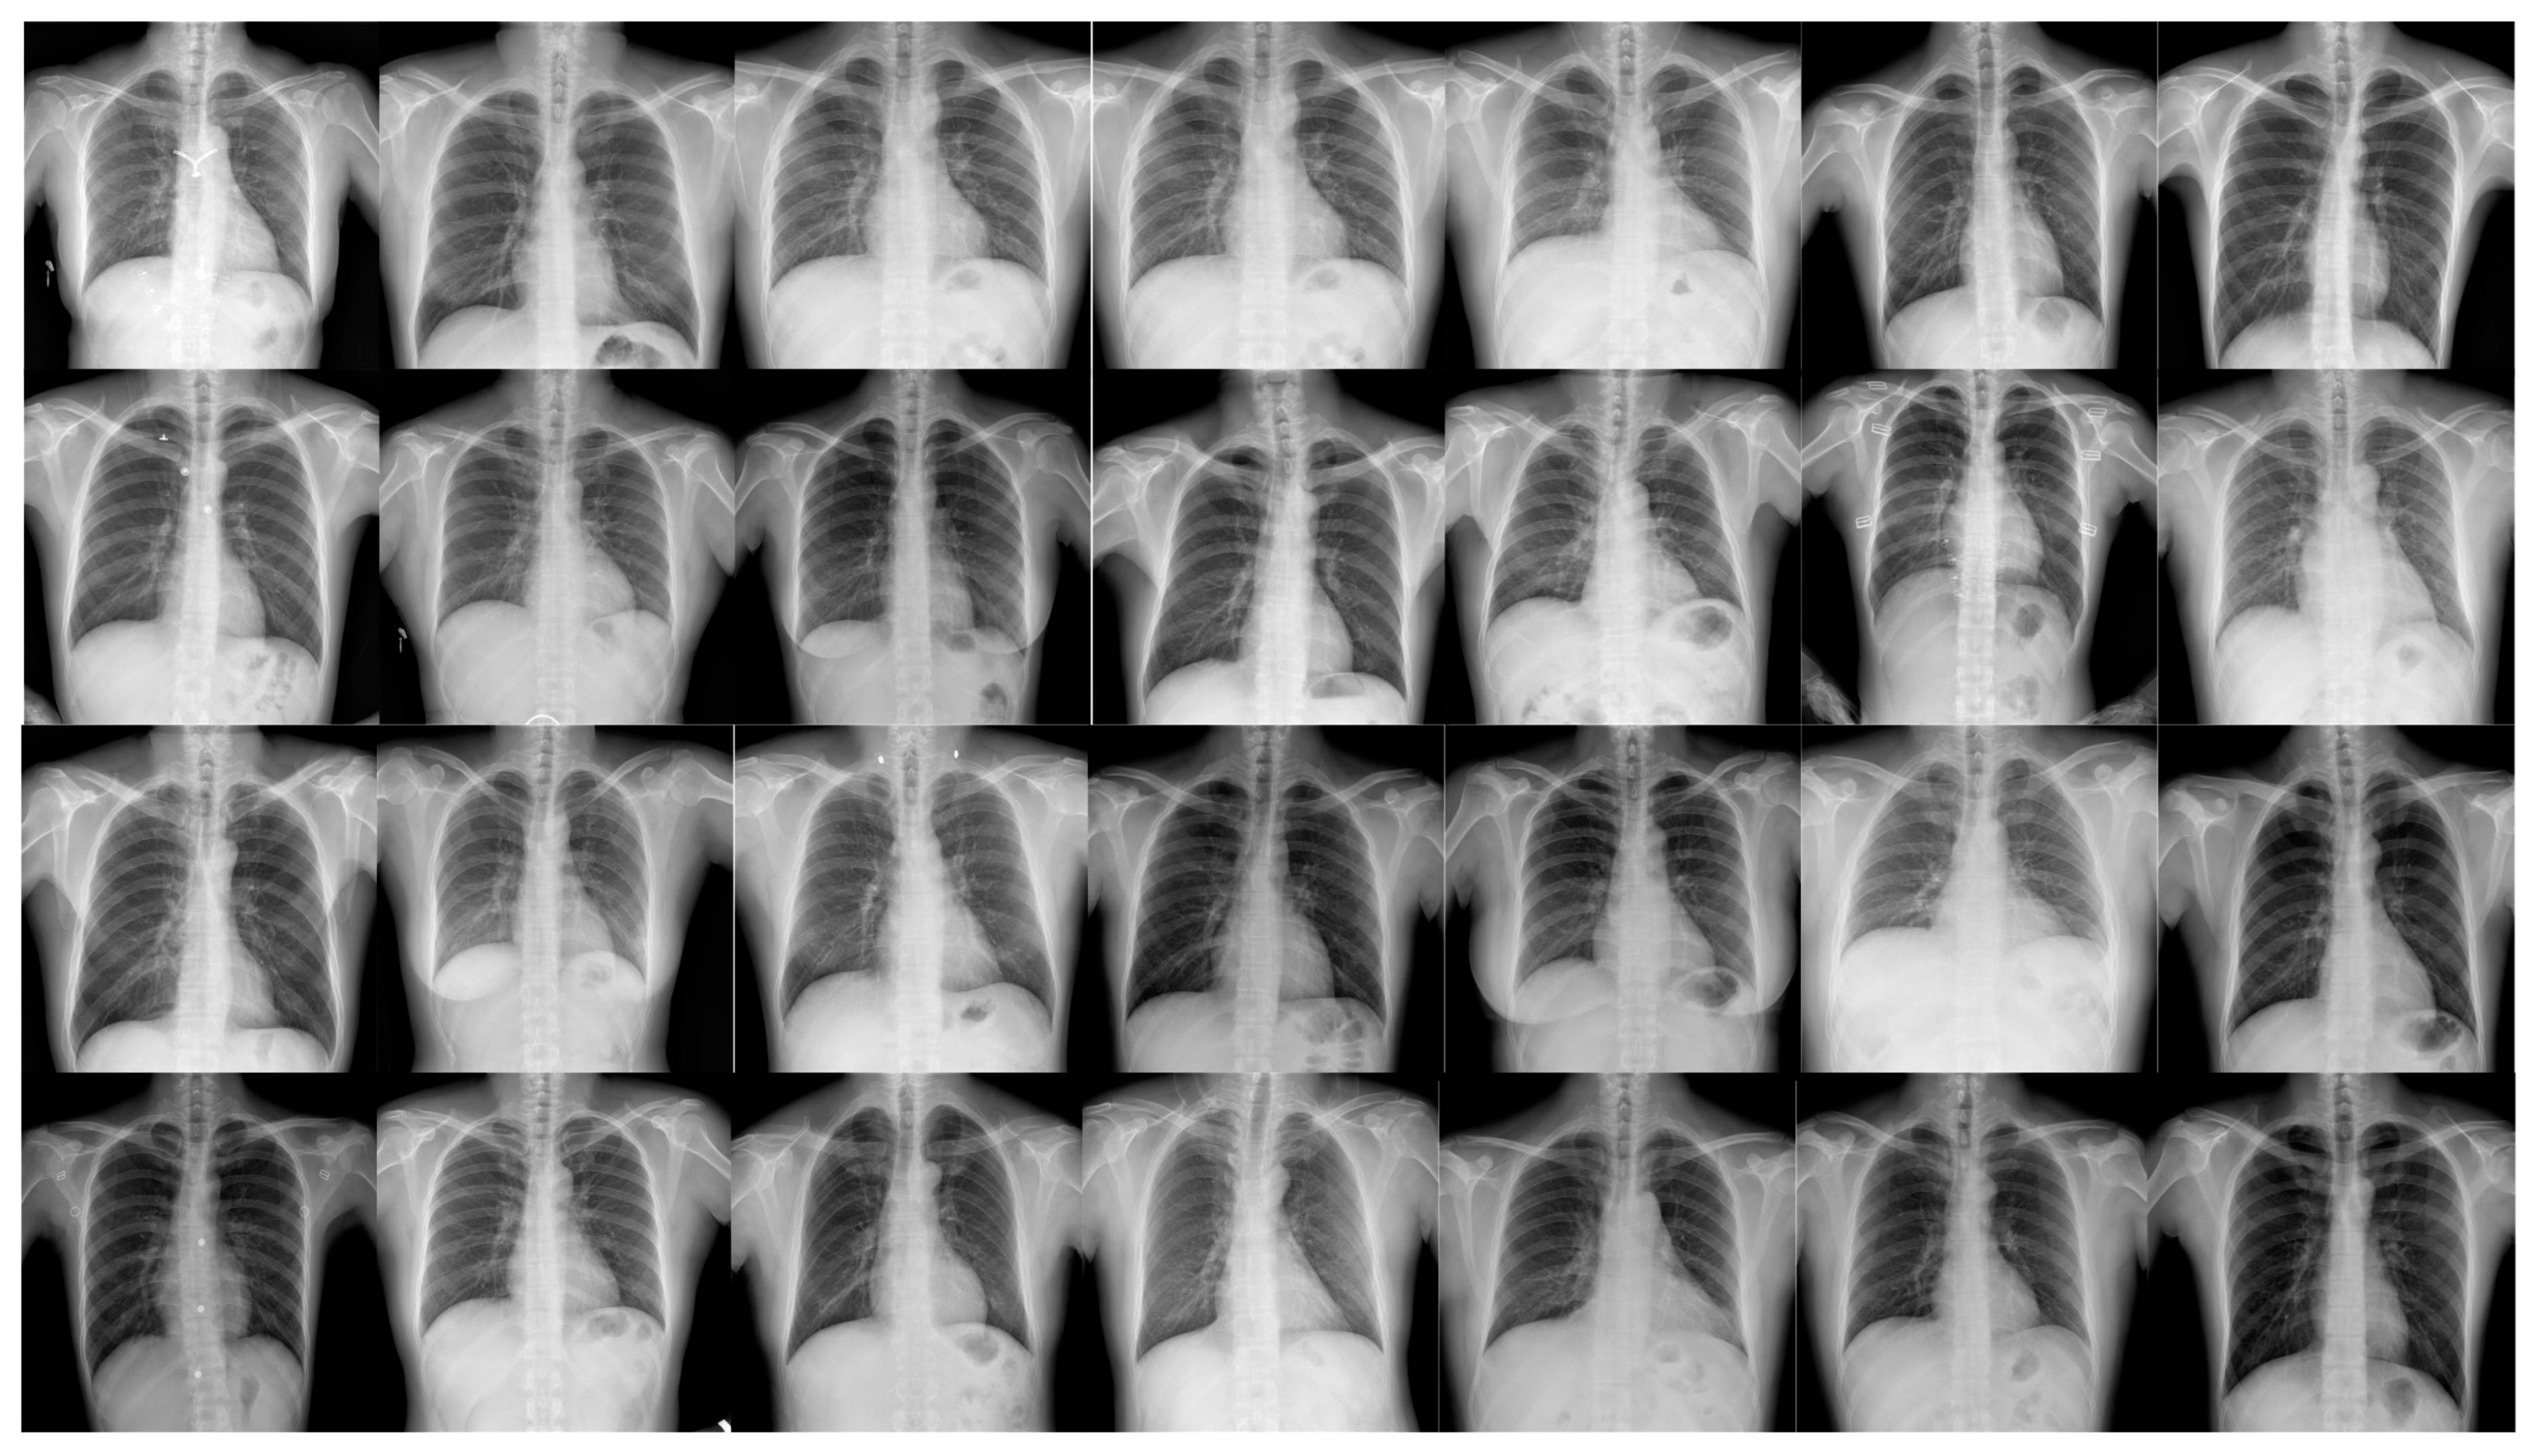

X-ray images of pneumonia typically exhibit complexity, diversity, and low contrast, necessitating the construction of an efficient and accurate pneumonia X-ray image dataset [13,14,15]. We used the open-source MIMIC Chest X-ray pneumonia dataset; the images were re-annotated using the LabelImg tool (as detailed in Table 1), which includes annotations for five categories: bacterial pneumonia, viral pneumonia, illness, healthy, and tuberculosis.

In this paper, we propose a targeted online data augmentation method. This method integrates several advanced image enhancement techniques, including Mixup and Mosaic, for comprehensive dataset preprocessing, significantly improving the model’s generalization ability and robustness [16,17,18,19].Annotated examples from the pneumonia dataset are shown in Figure 1. Specifically, the data augmentation process involved HSV transformation, translation, scaling, horizontal flipping, random cropping, zooming, and stitching [20,21]. These techniques not only effectively increase the sample size but also enhance the model’s sensitivity and adaptability in small-object detection, providing strong support for the overall optimization of model performance.

Figure 1. Pneumonia detection dataset.